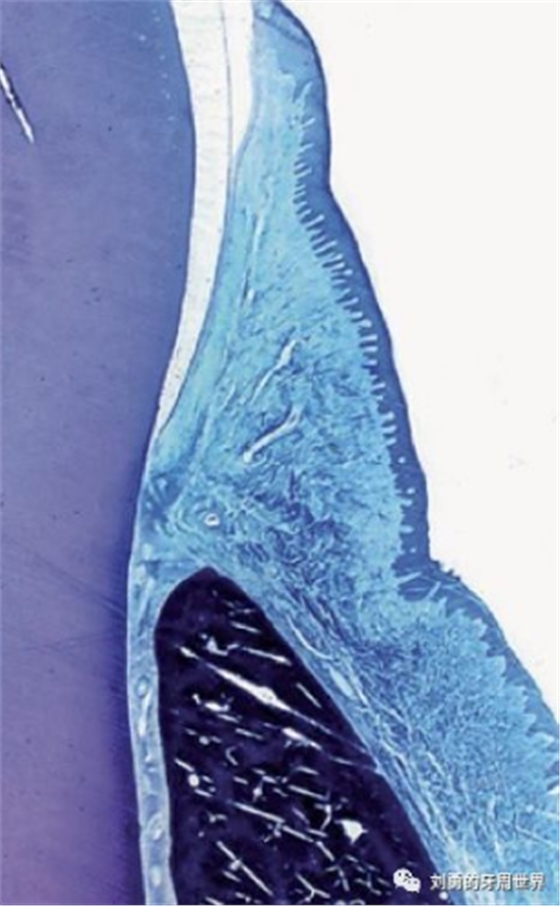

下面的這張切片也表明齦溝上皮是有釘突的。

但是再來看一張切片:

這張切片當中,在齦溝上皮的區(qū)域似乎看不到明顯的釘突。